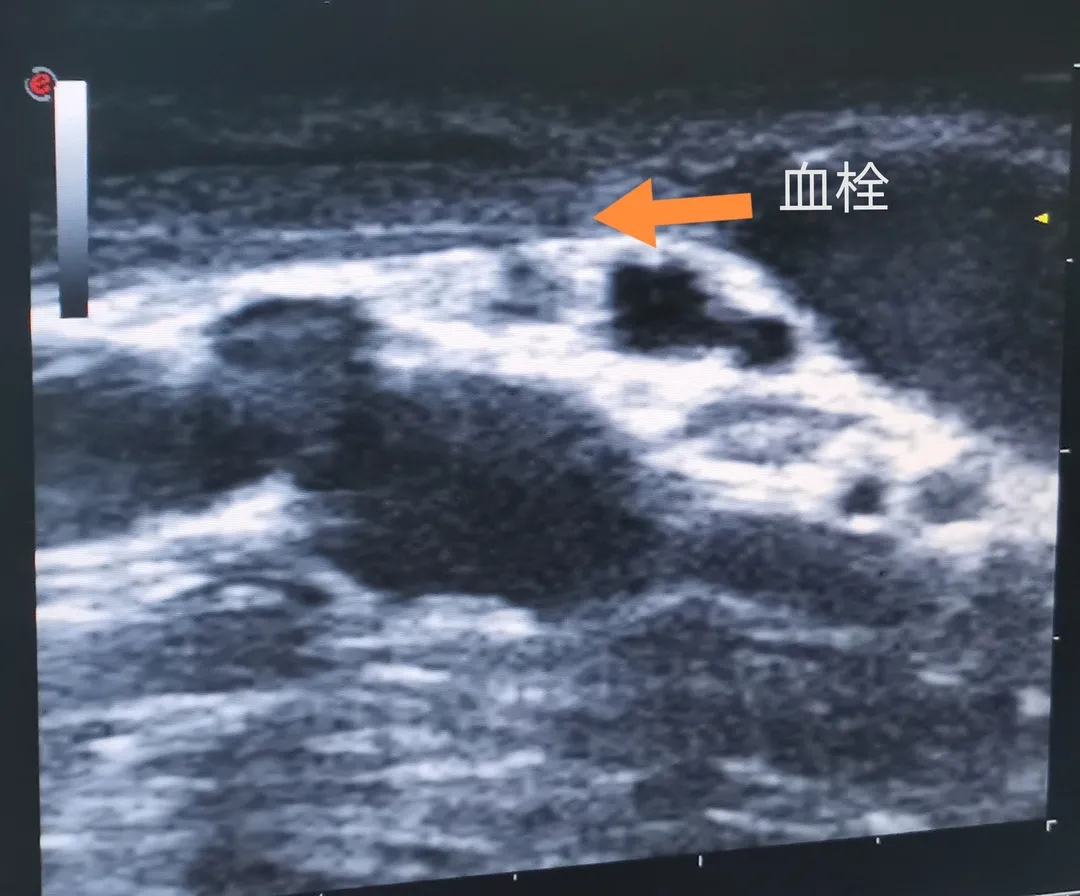

秦先生入院時,右上肢高位動靜脈內(nèi)瘺,貴要靜脈+頭靜脈雙流出道。瘺口震顫尚可,貴要靜脈穿刺點(動脈端穿刺點)局部震顫消失——考慮血栓形成。頭靜脈流出道局部迂曲明顯,雖有震顫,穿刺后流量僅維持在200ml/min。彩超示:肘正中靜脈—肱動脈端側(cè)吻合。貴要靜脈流出道起始部局部狹窄,血栓形成,長約2.5cm;頭靜脈流出道距離吻合口6cm處呈“Z”字型迂曲。肱動脈流量約400ml/min。

貴要靜脈血栓形成處